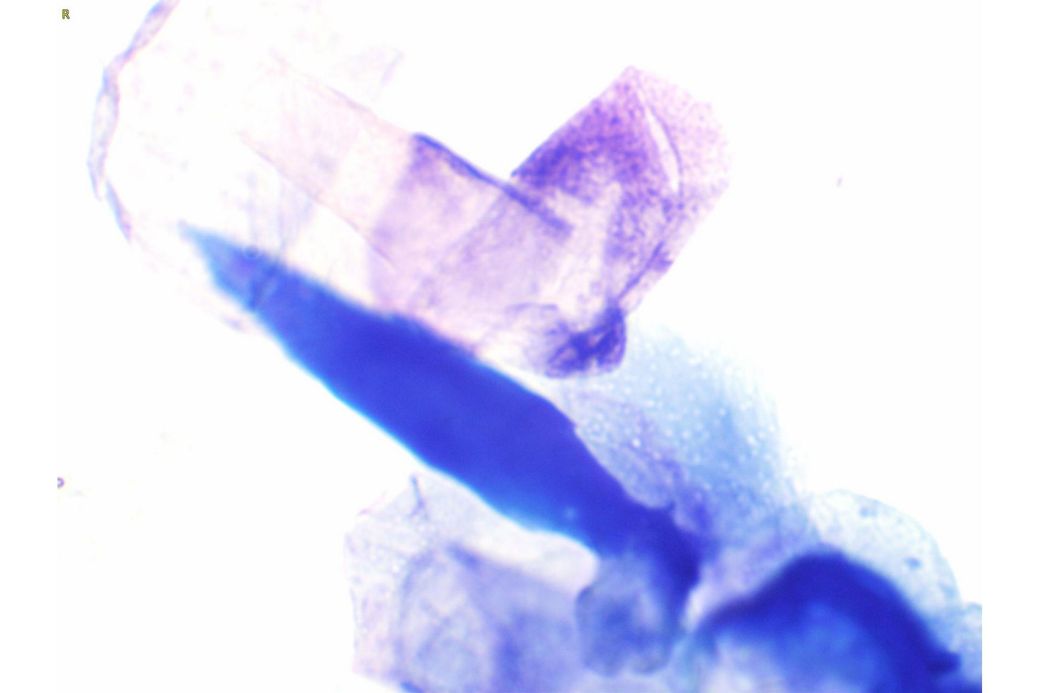

귀약도 사진만으로 어떤 약이 맞다고 정해드리기는 어렵습니다 외이염 치료는 보이는 모양만이 아니라 현미경 검사에서 세균인지 효모인지 귀진드기인지에 따라 달라지고 실제 수의학 자료도 이경 검사와 세포검사를 바탕으로 약을 고르라고 설명합니다 다만 통증과 부종이 심한 외이염에서는 스테로이드가 들어간 점이약이 부기와 통증을 줄이는 데 도움이 되기도 합니다 쿠싱이 있어도 바르는 약이 전신 먹는 약보다 몸 전체 영향은 적은 편이지만 아예 영향이 없다고는 못 하므로 정말 필요한지와 기간을 짧게 쓸지까지 같이 따져야 합니다